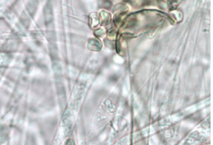

What is the larger black round structure being pointed at?

Sporangium

What are the smaller circular structures being pointed at by two arrows?

spores

What are the elongated thin structures being pointed at?

hyphae